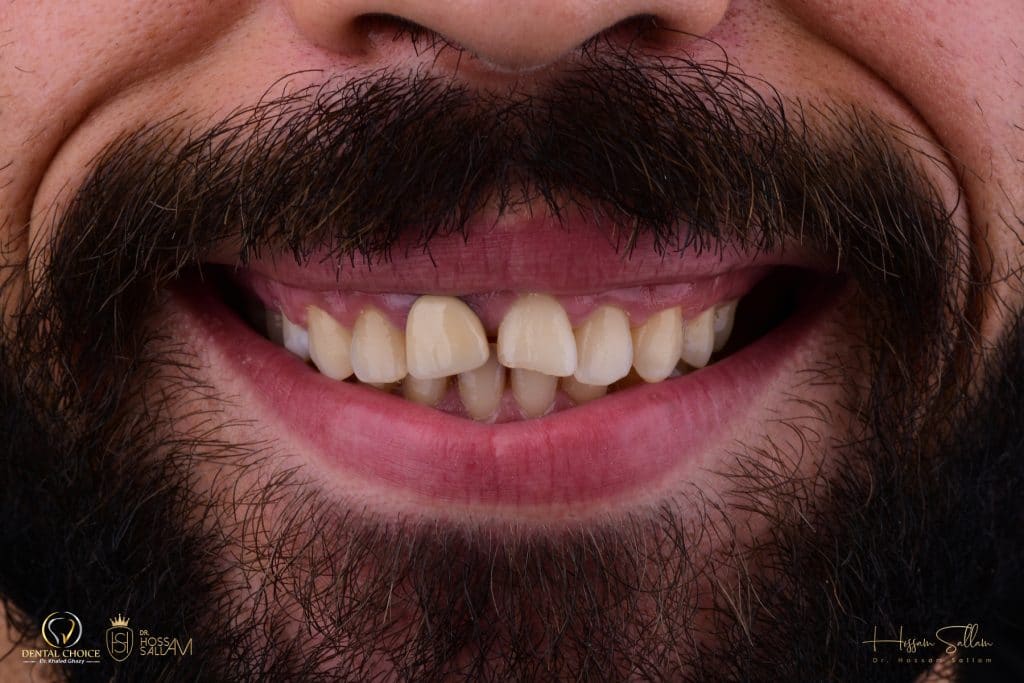

pre operative situation

This pic showing

- Reverse Smile line

- black shadow at buccal corridor region

- in accurate teeth ratio

- gum Smile specially at posterior region

- inadequate zenith position

Smile right

smile left